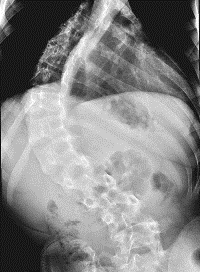

نجح فريق طبي في مستشفى الملك خالد الجامعي في إنهاء معاناة مريض في الثالثة عشرة من عمره أصيب بالشلل نتيجة انحراف شديد في العمود الفقري (الجنف) وتأخر في العلاج حتى وصلت نسبة الانحناء إلى (140درجة). هذا، وقد تم تنويم المريض بشكل عاجل وأجريت له عملية جراحية لإزالة الضغط عن الحبل الشوكي وتم تقويم الظهر من الخلف حيث تمكن المريض من المشي والعودة لممارسة حياته الطبيعية بعد العملية مباشرة ولله الحمد.

وذكر الدكتور عبدالمنعم الصديقي الأستاذ المساعد بكلية الطب واستشاري جراحة العظام والعمود الفقري بمستشفى الملك خالد الجامعي ورئيس الفريق الطبي لوحدة الجراحات التقويمية للعمود الفقر (الجنف) أن الانحرافات في العمود الفقري تعد من الأمراض الخطيرة والمعقدة في أي مجتمع، ونظراً لندرة المراكز الطبية و ندرة المتخصصين في هذا المجال، فإن ذلك أدى إلى تأخر العديد من المرضى في تلقي العلاج ووجود صعوبات كثيرة في تعديل وتقويم هذه الانحرافات حيث تزداد نسبة الانحراف كلما تقدم بالمريض العمر وتأخر العلاج.

أما عن تنوع الحالات فيذكر الدكتور الصديقي أنه تم عمل أربع حالات عن طريق شق الصدر وإرخاء العمود من الأمام وذلك لشدة انحراف العمود الفقري حيث بلغ في إحدى الحالات (140 درجة)،

وكذلك تم عمل حالتين عن طريق عمل فتحة في البطن لشدة الانحراف، أما أكثر الحالات فكانت تحتاج إلى تثبيت وتقويم للعمود الفقري من الخلف فقط، ومن الحالات النادرة كذلك حالة لطفل في السابعة من عمره تم فيها استئصال فقرة كاملة من الخلف كانت ضاغطة على الحبل الشوكي.